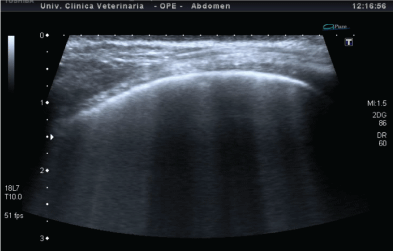

肺滑动是一种动态的超声征象,在胸膜线上可观察到,是患者呼吸时肺胸膜在胸膜壁层上滑动而产生的。这种运动提示两胸膜组织的生理接触[12-15]。b线由从胸膜线开始并垂直于胸膜线的高回声线表示,这些高回声线与患者呼吸同时运动,并以相同的强度贯穿扫描深度(图2)。这些线突出肺泡间质综合征的存在,这可能是由于血管外水的存在,如肺水肿或间质厚度增加[9,16,17]。在人类医学中,b线的数量随着疾病的严重程度而增加,从而导致呼吸困难,并与胸片上的肺充血体征直接相关[18-20]。

图2:胸壁;从胸膜线开始,一些高回声线(b线),由于环形的人工制品,是明显的;心源性肺水肿患者胸膜规则,无增厚